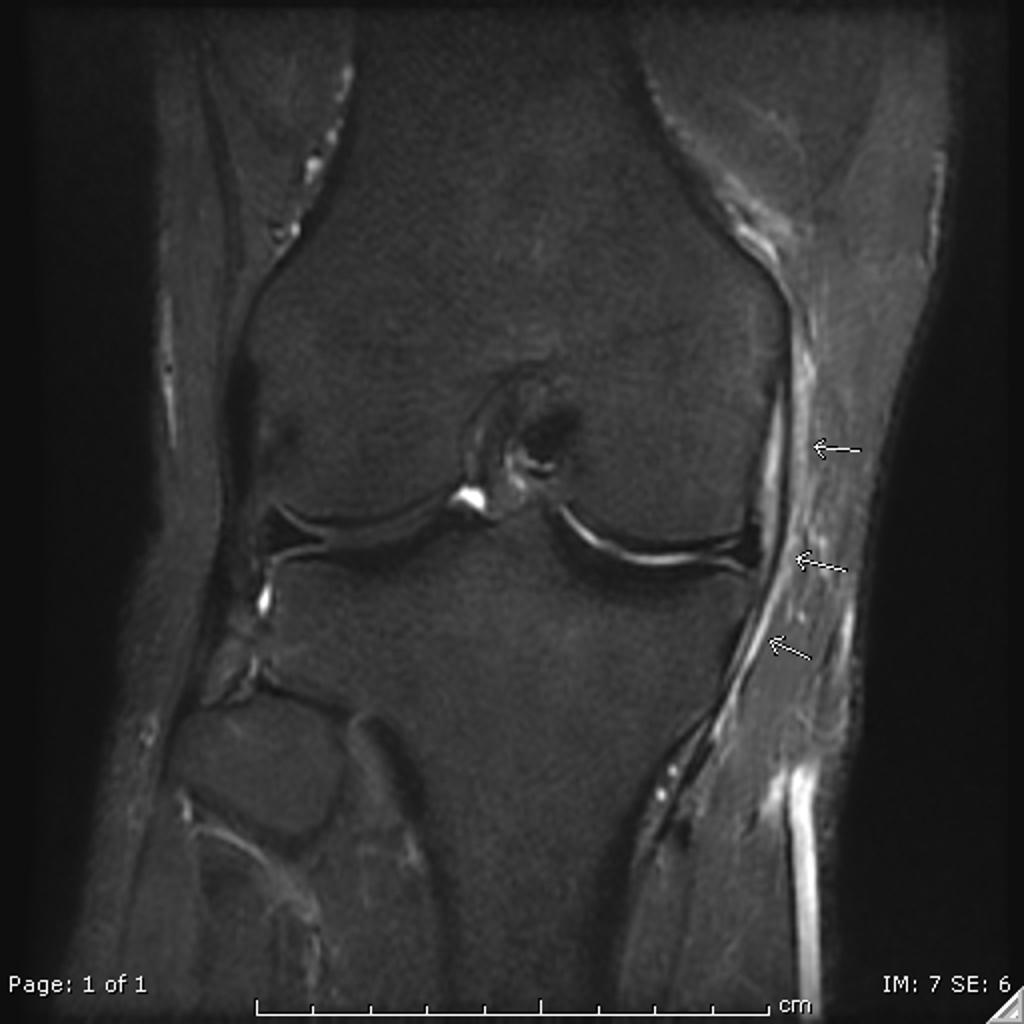

The medial collateral ligament is seen surrounded by edema, with normal thickness and signal intensity of its fibers’ abd no loss of continuity.